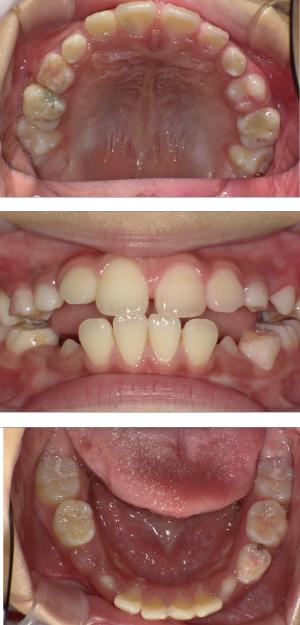

バイオブロック矯正(顎顔面口腔育成治療)

矯正治療は大人になって始めるよりも子どもの頃から始めた方が確実に良い結果をもたらします。成長が盛んな子供の時期に、顎や顔の成長を利用しながら治療ができる大きなメリットがあるからです。当院では、非抜歯矯正を推奨しておりバイオブロック矯正を取り入れています。

バイオブロック矯正の考え方は歯並びが悪くなる原因にアプローチする治療法になります。

舌の位置や口呼吸から乱れてしまった下顎の後退を正し、顎顔面が本来あるべき位置へと誘導させていく治療です。

- 歯並びの改善